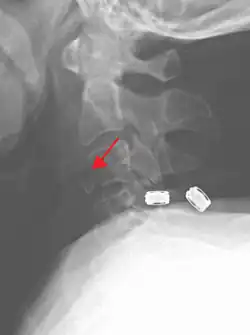

On CT scan or X-ray, a cervical fracture may be directly visualized. In addition, indirect signs of injury by the vertebral column are incongruities of the vertebral lines,[7] and/or increased thickness of the prevertebral space:[8]

![CT scan of normal congruous vertebral lines[7]](./_assets_/Vertebral_lines.png)